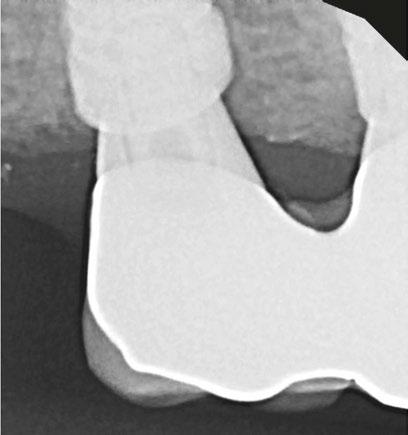

A CBCT scan was taken and panoramic views of the maxilla and mandible evaluated (Figure 3). Bilateral pneumatization of the maxillary sinus was noted, but adequate bone height was present between the premolars for implant placement to support an All-on-X hybrid prosthesis. In the mandibular arch, sufficient height was available between the mental foramen bilaterally and over the inferior alveolar nerve for implant placement to also sup port an All-on-X fixed hybrid prosthesis. A discussion was held with the patient that implants could be placed in both arches that would allow restoration with fixed prosthetics. Should sufficient insertion torque be achieved at the time of implant placement, a screw-retained hybrid provisional prosthesis would be placed and worn for several months during healing after which a final prosthesis would be fabricated. The patient would also be able to do a “trial-run” of the esthetics with the provisional prosthesis, with any requested modifications made when the final prosthesis was designed and fabricated. The treatment plan included six implants in each arch to support the planned hybrid prosthe ses. The patient was informed that reduction of the crestal bone would be required to achieve a flat ridge for adaptation of the prosthesis to the ridge as well as to provide adequate interarch space for the final prosthesis. The patient accepted the treatment plan. An intraoral scan of the arches was performed with Medit i500 (Medit Corp, Seoul, Korea) as well as the current complete arch maxillary and mandibular dentures (Figure 4). The patient was dismissed and scheduled for the surgical appointment.

The scans were imported into the planning software (Real GUIDE™, Allston, Massachusetts) and merged with the CBCT scan to allow implant planning. The maxillary arch was planned for implants at six sites, including tilted implants mesial to the maxillary sinus bilaterally to avoid the need for sinus augmen tation and allow more distal placement of the implant platform for a better anterior/posterior (A-P) spread (Figure 5A). ULT implants were planned as follows: No. 3 (3.75 x 11.5 mm), No. 6 (3.75 x 11.5 mm), No. 8 (3.75 x 11.5 mm), No. 9 (3.75